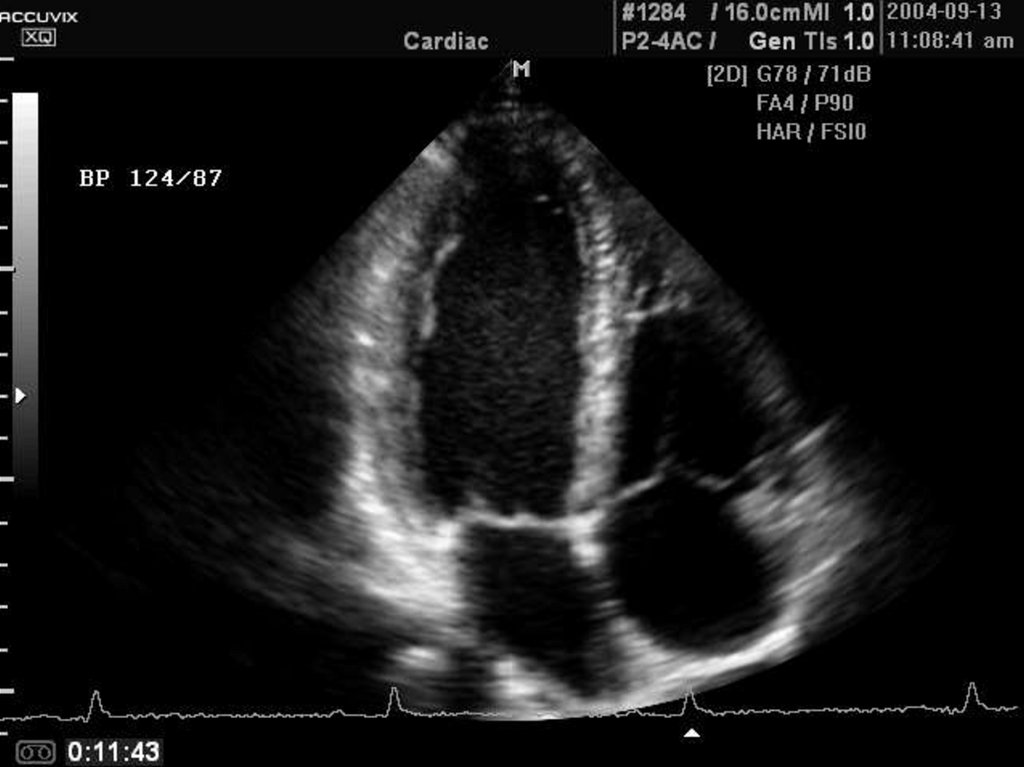

Строение сердца